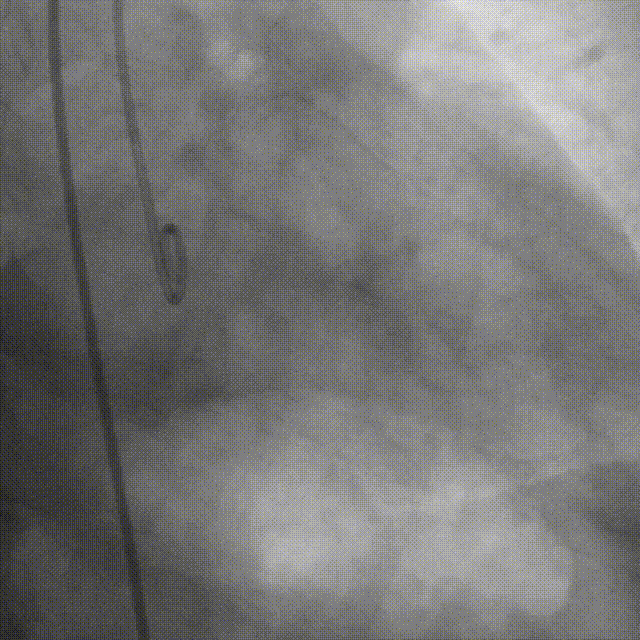

手术过程

瓣膜定位,0位释放

释放2/3处造影确认植入深度